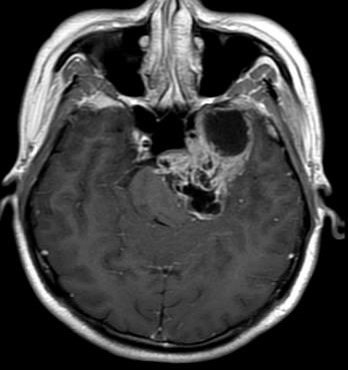

巨大中后颅窝沟通哑铃型三叉神经鞘瘤的手术治

348x370 - 20KB - JPEG